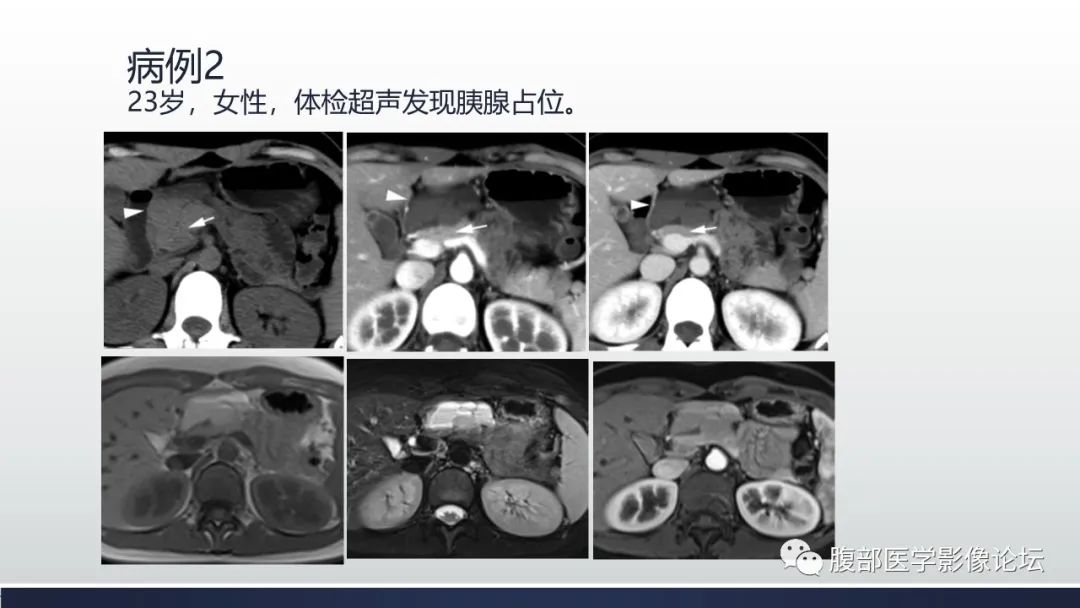

【病例】胰腺血管瘤1例CT及MR影像-12

【病例】胰腺血管瘤1例CT及MR影像-13

【病例】胰腺血管瘤1例CT及MR影像-14